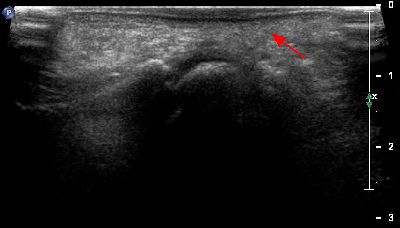

Microavulsione tendine peroneo breve microavulsione tendine peroneo breve